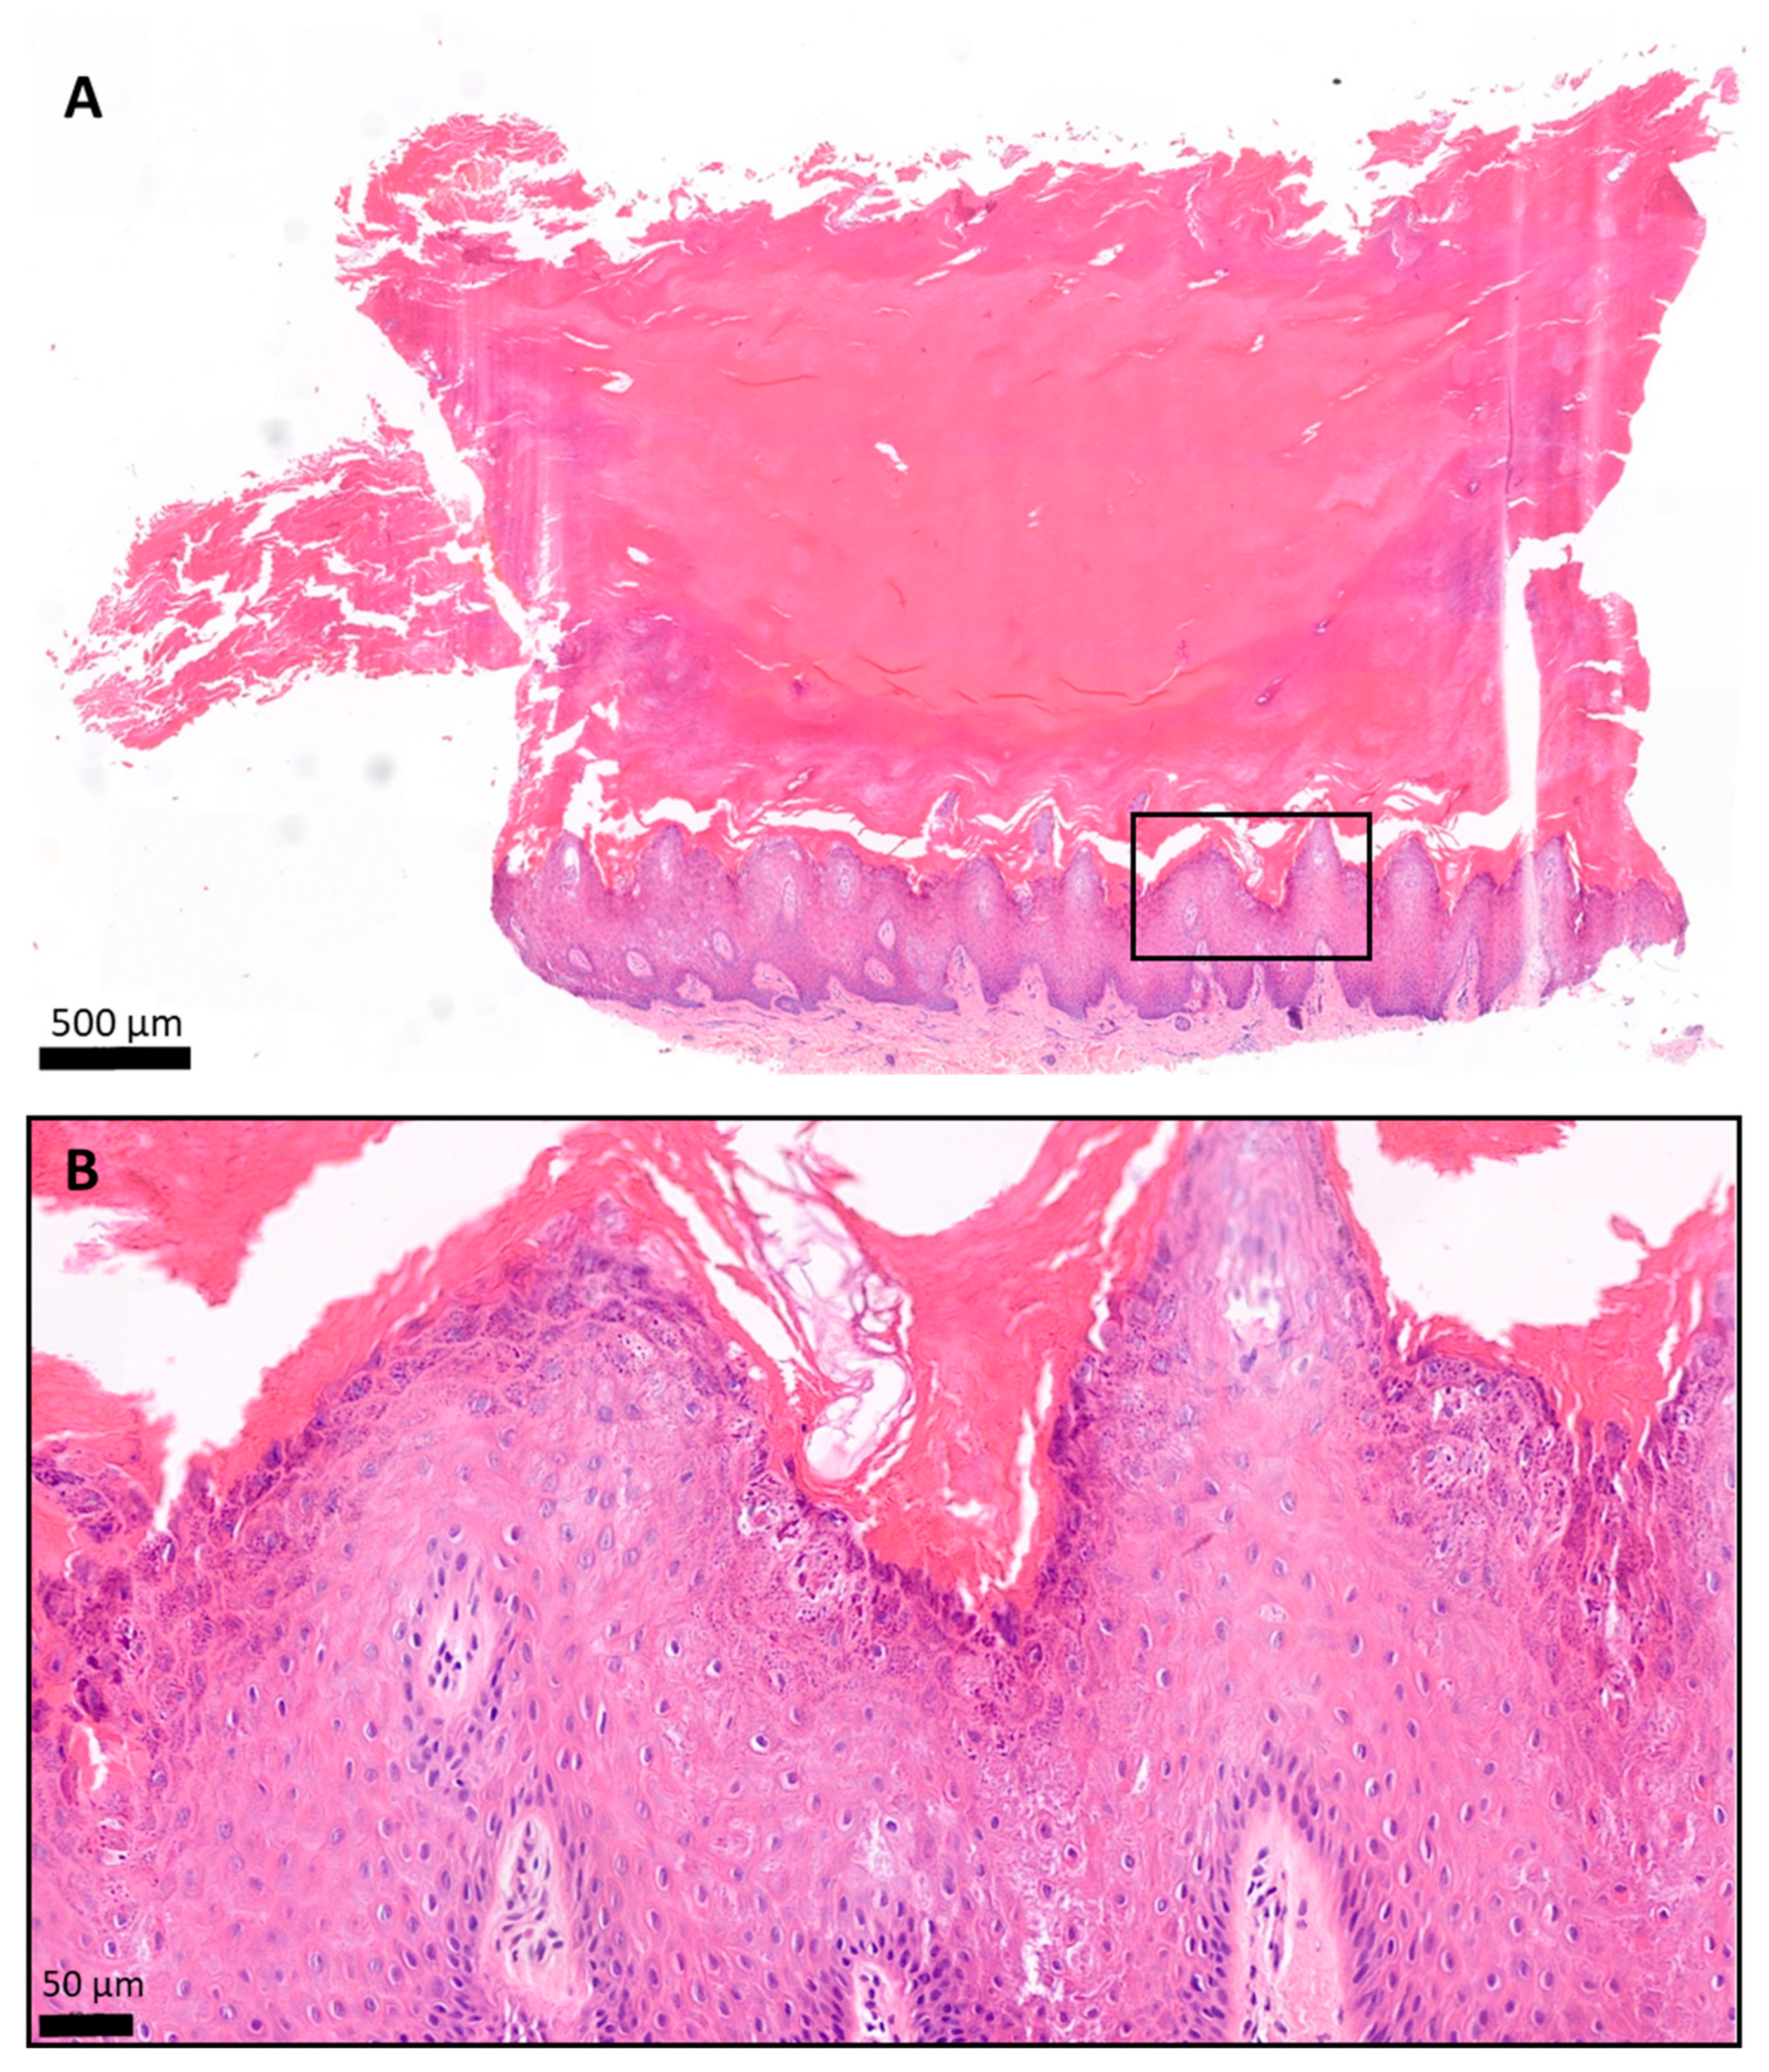

3.4. NLM Imaging and Histology